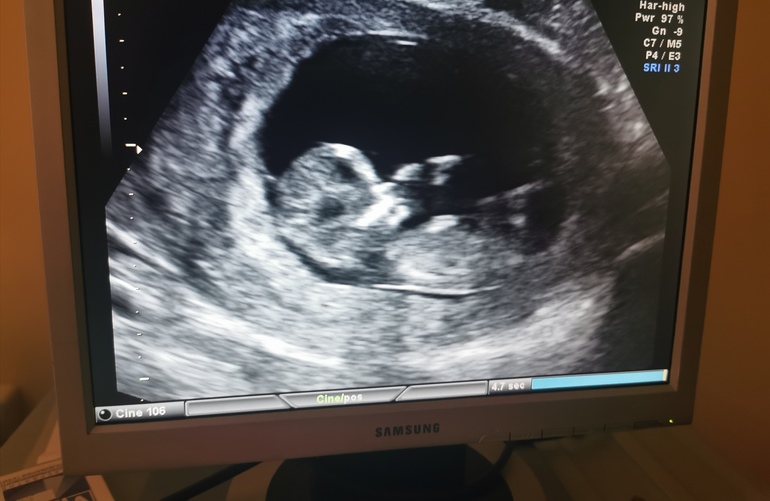

Наш первый скрининг ❤️❤️❤️

Риски минимальные. Это радует. Наша бусинка подрос или подросла на 16 мм за неделю. По месячным нам 11 и 5. По узи плода 12 и 4. Хорион также по задней стенке и перекрывает зев. Но сказали, такое бывает часто. Малыш 60 мм. Все органы на месте. Толщина воротникового пространства 1,3 мм. Теперь ждем результат крови. Пол не сказали, я и не настаивала. Главное с ним все хорошо. ❤️❤️❤️❤️

Лучший подарок на новый год ❤️❤️❤️❤️❤️